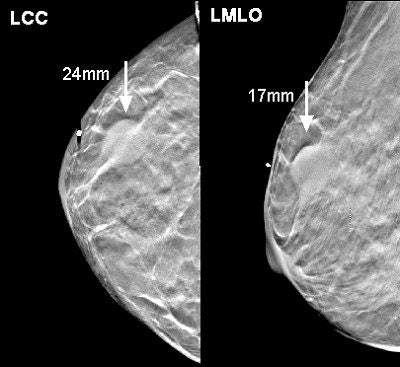

![]() |

| Above, conventional mammogram on which cancer is obscured. Below, DBT slice on which cancer is clearly defined. Images courtesy of Richard Moore and Dr. Daniel Kopans. |